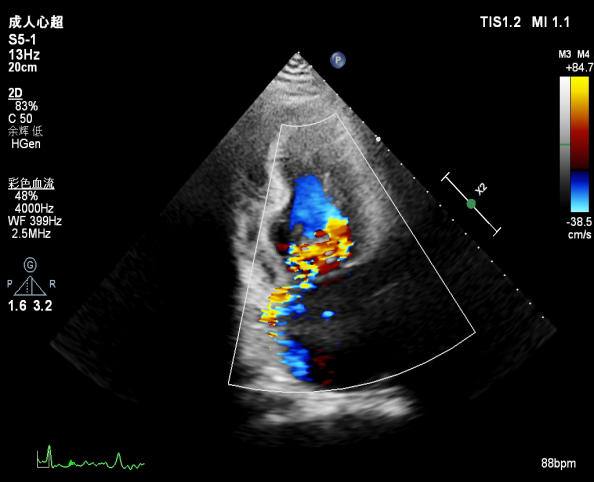

肺静脉血流频谱逐渐恢复正向,后测量平均跨瓣压差:2mmHg

肺静脉血流频谱恢复正向

二尖瓣瓣口平均跨瓣压差:3mmHg